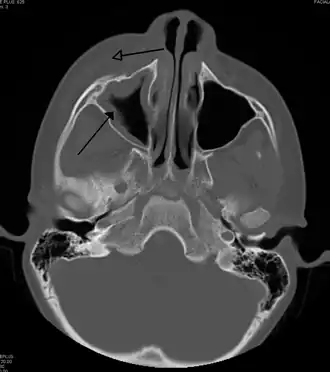

For sinusitis lasting more than 12 weeks, a CT scan is recommended.[66] On a CT scan, acute sinus secretions have a radiodensity of 10 to 25 Hounsfield units (HU). In a more chronic state, they become more viscous, with a radiodensity of 30 to 60 HU.[69]

CT of chronic sinusitis

CT scan of chronic sinusitis, showing a filled right maxillary sinus with sclerotic thickened bone